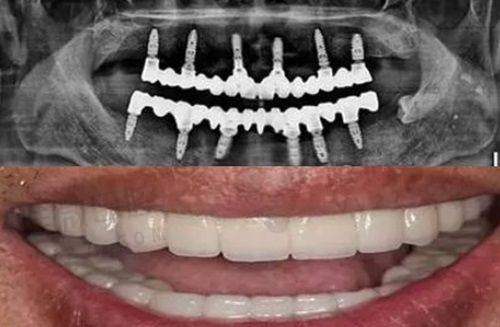

半口种植套餐:39800元起,全口种植:68000元起

包含4~6颗种植体+12~14颗牙冠+导板设计,需要全口修复的长辈强烈推荐,不用戴磨人假牙,术后当天就能进食,一次搞定无法咀嚼的老烦恼。